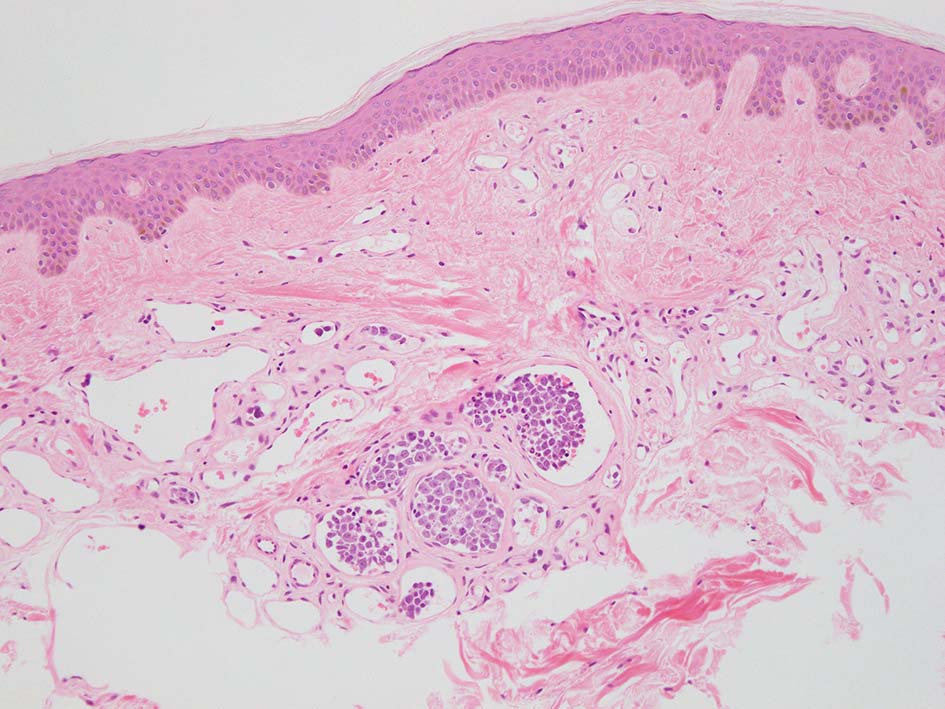

この症例は皮膚, cherry spotとよばれる老人性血管腫の血管内に腫瘍細胞集簇を認めた. (老人性血管腫はよい生検スポットといわれていたが, 必ずしもそうとはいえないらしい)

皮下脂肪織,細血管内の腫瘍細胞. 大型多型細胞より若干小さめの腫瘍細胞も認められる. CD20を先に染めておくと病変の有無がわかりやすい. HEだけで安易に「病変なし」としないほうがよい.